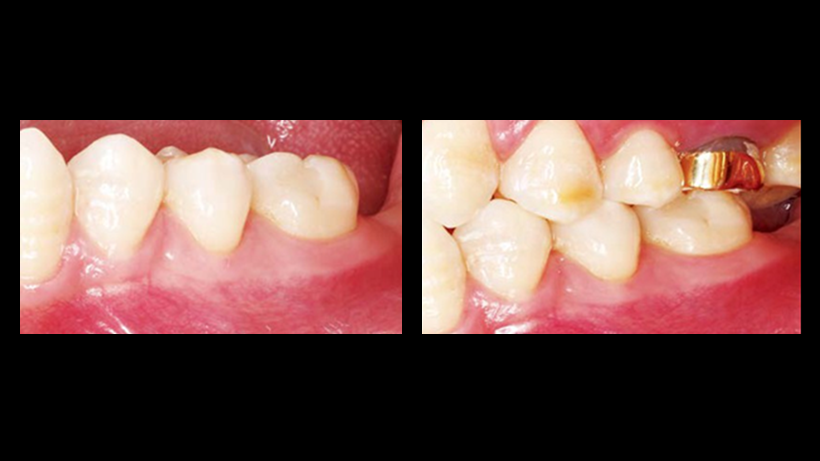

Clinical case: Immediate post-extraction insertion of implant & immediate loading

- Courtesy of Prof. Giuseppe Luongo, Italy -

AnyRidge, immediate loading, single implant, multicenter study, maxillary anterior, Prof. Giuseppe Luongo, single replacement